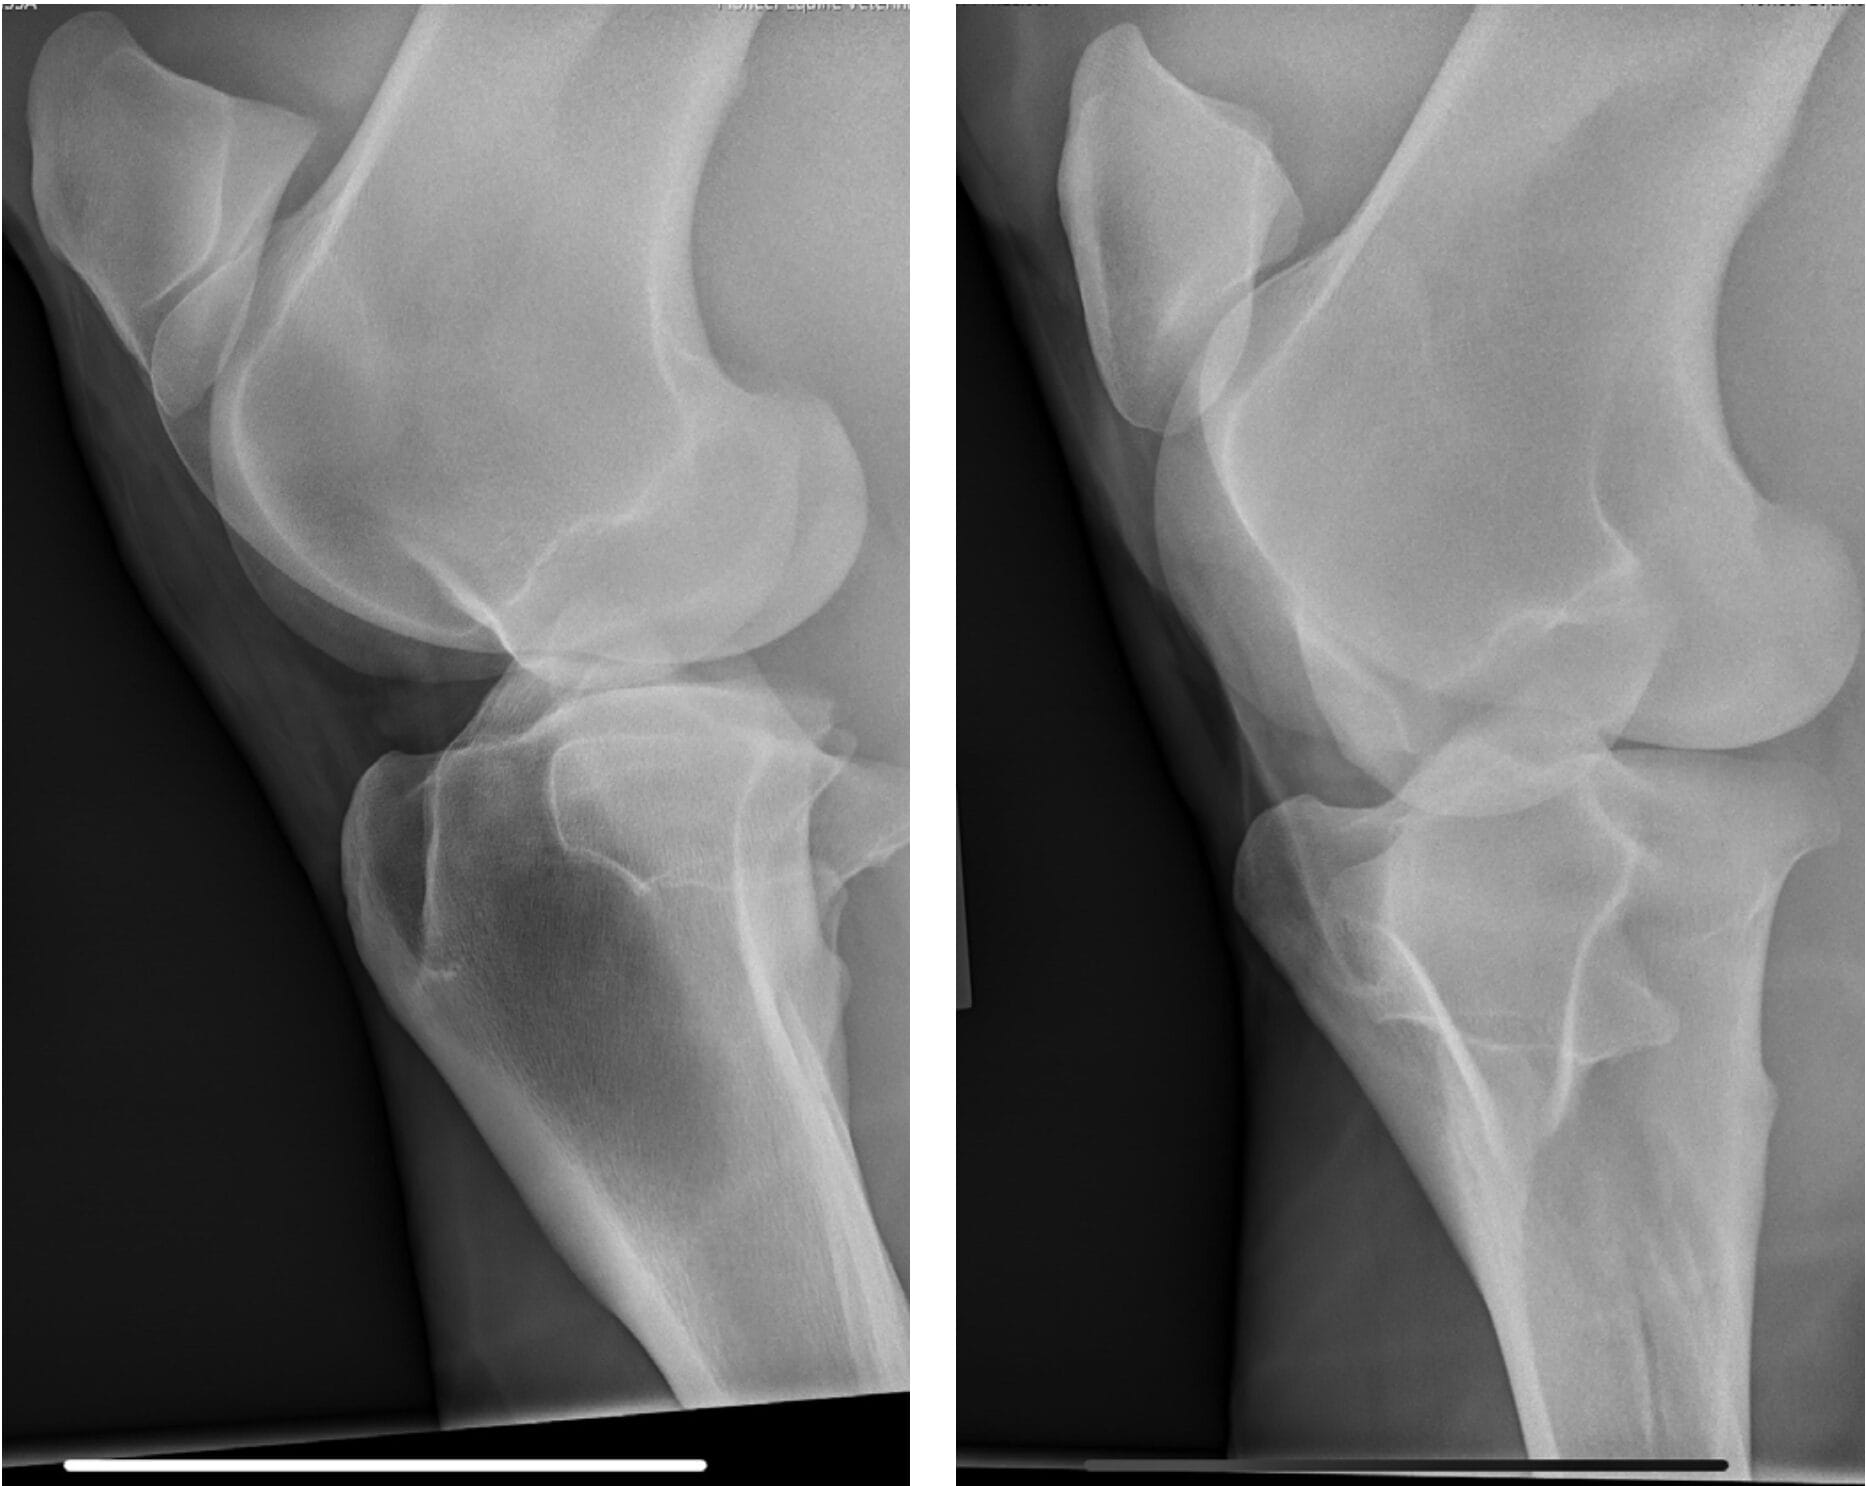

In April 2023, Bella developed a right hind lameness that was characterized by a toe drag, decreased push and mild abduction of the limb. The lameness was worse with the leg on the outside of the circle. She was negative to lower limb flexion and 1+ out of 5 positive to upper limb flexion. Lameness resolved with an intra-articular medial femorotibial block. Radiographs of the right stifle were unremarkable.

Ultrasound of the right stifle showed moderate medial femorotibial joint effusion with small hyperechoic particles, consistent with thin cartilage debris. There was a 1.5 cm x 0.5 cm defect in the abaxial portion of the medial trochlear ridge.